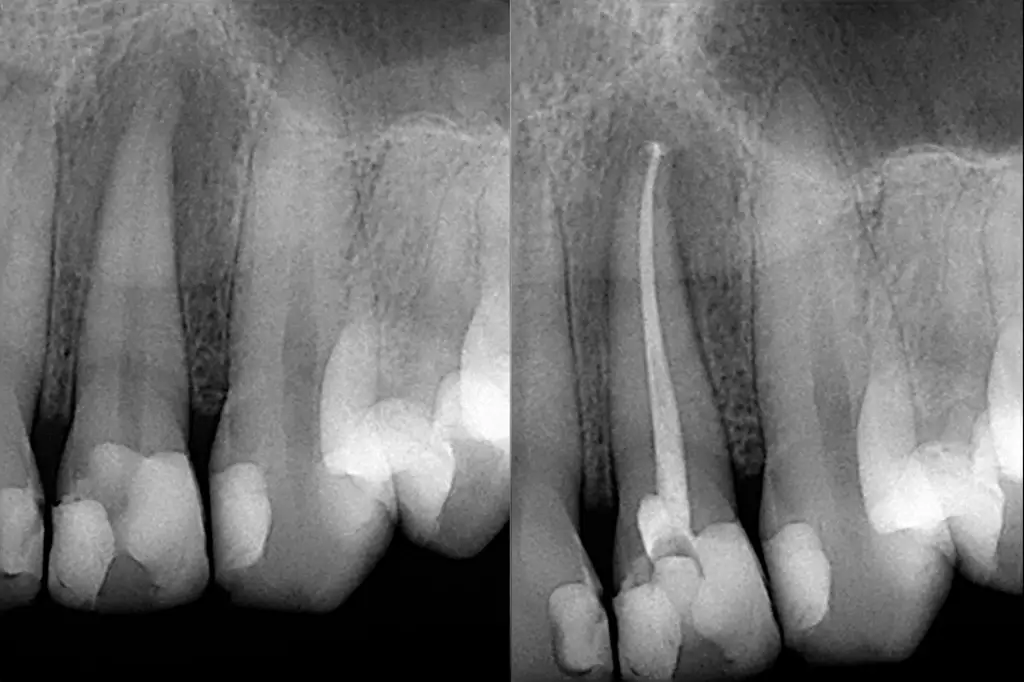

Root canal treatment doesn’t need to feel daunting. At Style Dental Noosa, we use modern techniques and gentle anaesthesia to treat infection, relieve discomfort, and preserve your natural tooth structure with confidence.

- Precise digital imaging for accurate diagnosis